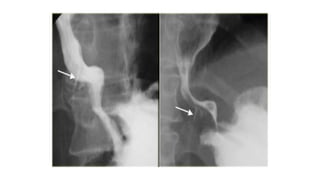

LEFT: Small polypoid carcinoma. RIGHT: Large polypoid lesion.

LEFT: Small polypoidcarcinoma. RIGHT: Large polypoid lesion.